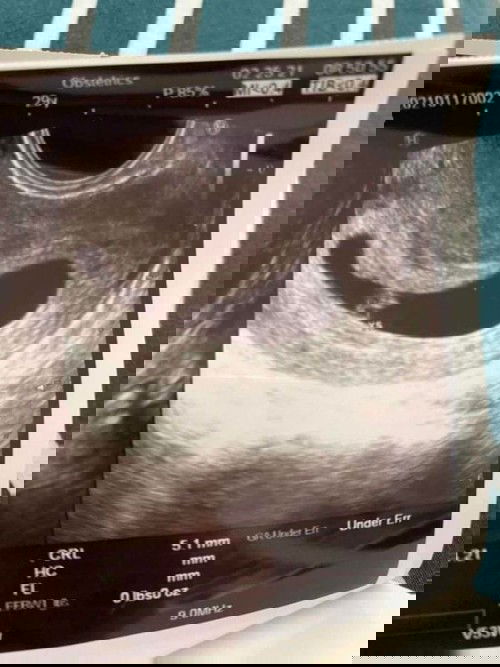

Irregular Gestational Sac

Hello mommies! Just had our ultrasound today and sabi po samin irregular daw po shape ng gestational sac. Currently 6w4d po ako ngayon. Twin pregnancy po. Meron na din nakitang yolk sacs, embryos and heartbeats. Worried lang po sa irregular shape ng gestational sac. Sino po naka experience dito ng same shape po ng akin? Thank you po sa mga sasagot